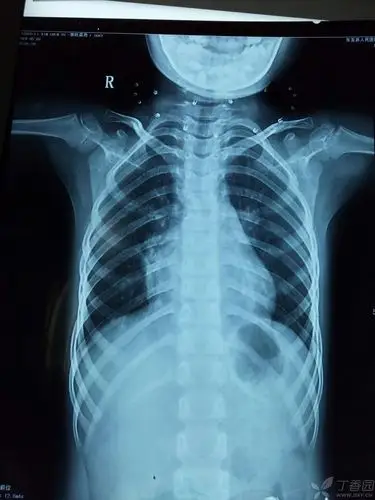

双胞胎反复肺炎的原因,及下一步处理. [病例帖]